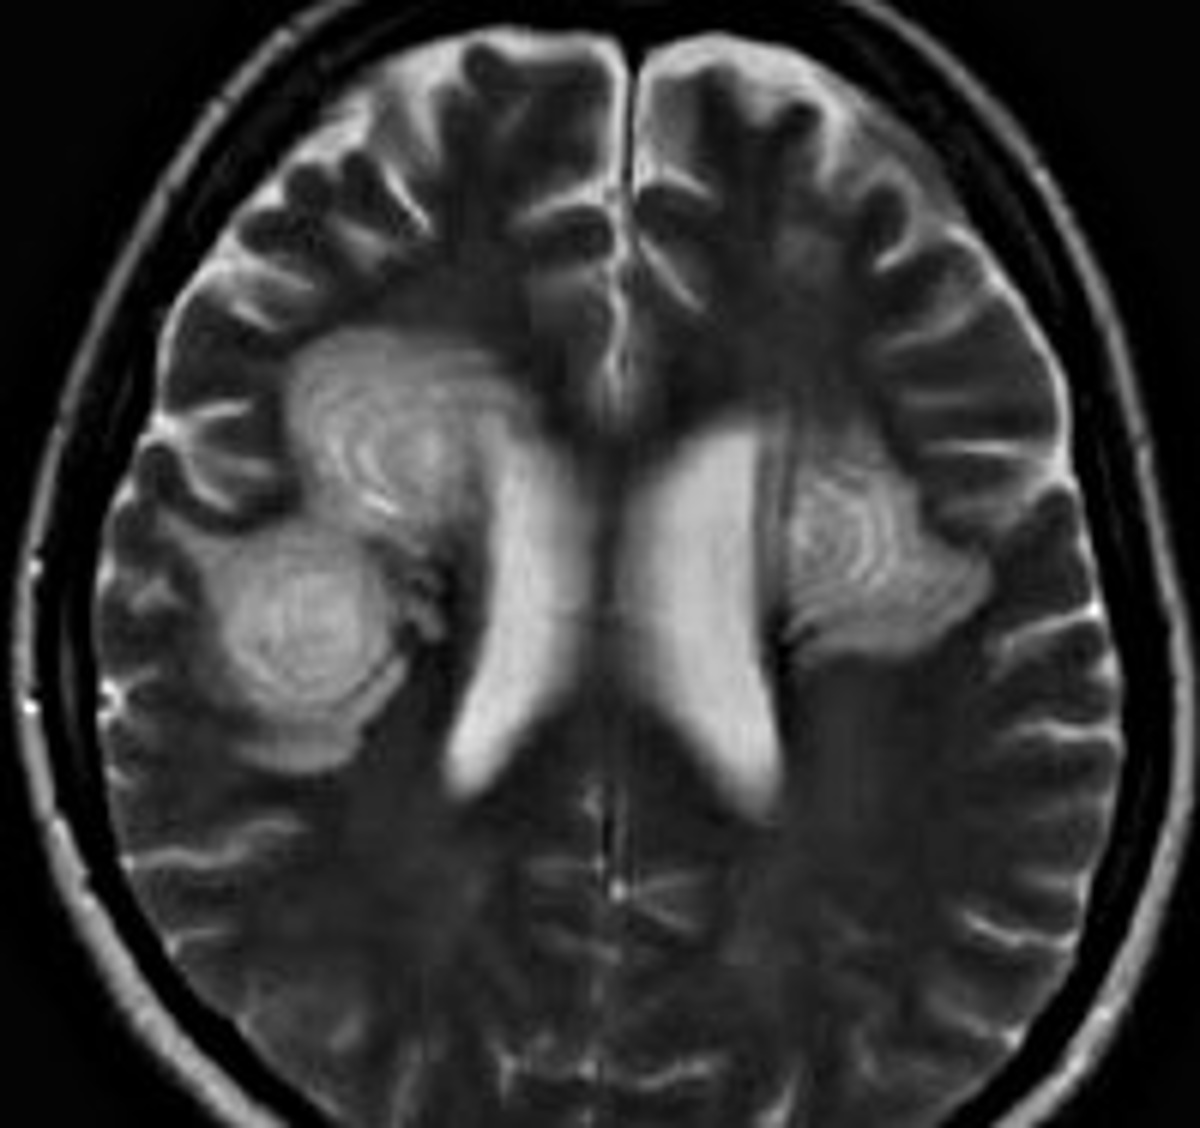

Демиелинизирующие заболевания мозга: МРТ изображения